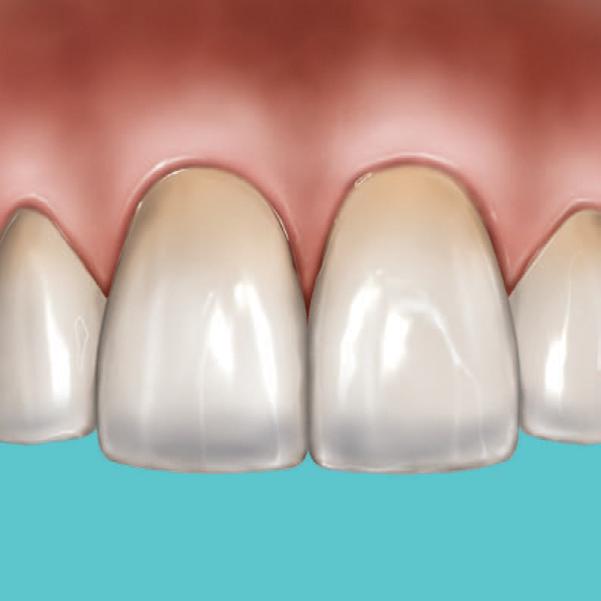

A significant number of people are unhappy with their smile, which has a considerable psychosocial impact. Although many seek cosmetic dental treatment, costs, fear and duration of total treatment are often barriers to the patients. Nevertheless, many could benefit from small and subtle changes to their teeth. With simple direct and freehand techniques, quick but significant results can be obtained that ultimately greatly improve the overall smile aesthetics.

The restoration of abfractions in the anterior area is important for aesthetic appearance especially in patients with high smile lines. Moreover, restoring abfractions strengthens the cervical area of the tooth, prevents further loss of enamel and ameliorates unpleasant sensitivity.

Worn canine cusp restoration is of special functional importance. Creating functional canine guidance with a minimally invasive composite addition to the canine cusp will protect the posterior teeth during lateral movements of the jaw. Incisal wear restorations return the youthful appearance to the smile and prevent further loss of enamel and exposure of the dentinee.